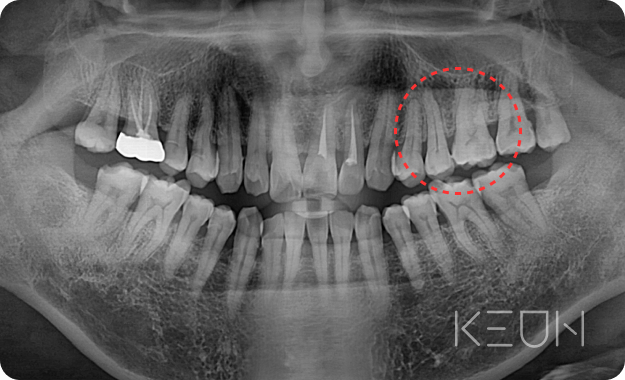

- Before

- After

신경 재치료

신경치료 근관의 개수, 길이, 굵기 등을 측정한 후 치수를 제거하고 근관을 세척해 미세한 근관까지 소독한 후 근관 충전을 하는 방식으로 치료합니다. 그러나 치료 후에도 지속해서 통증이 남아있다면 신경재치료가 필요합니다.